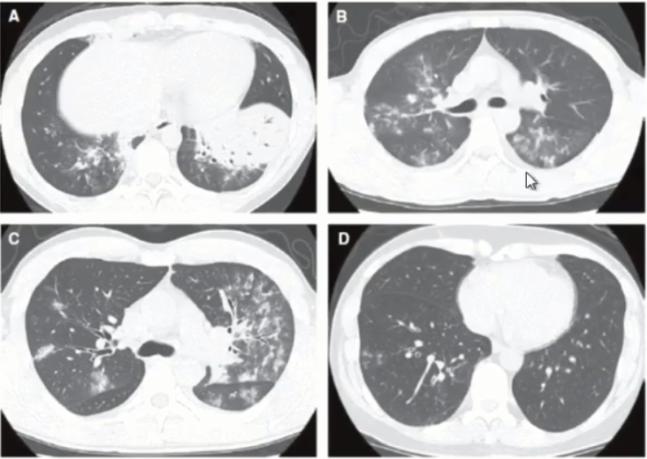

支原体肺炎和肺炎链球菌肺炎的CT影像区别

(1)支原体肺炎的特征性CT表现:磨玻璃渗出影;小叶中心性结节;支气管壁增厚。

(2)实变和胸水在支原体肺炎中并不少见

(3)进展期重症支原体肺炎中实变更为常见,与肺炎链球菌肺炎难以鉴别

图11 有研究显示,肺炎支原体肺炎和肺炎链球菌肺炎实变发生率分别是61%和76%,两者之间的差异无显著统计学意义

图12 支原体肺炎影像学表现的多样性

图13 叶段实变往往是支原体肺炎进展期(重症)的表现